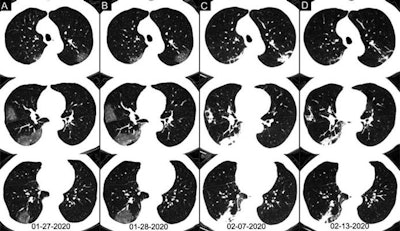

A recent examination of 51 cases demonstrated that CT had better sensitivity at detecting COVID-19 than RT-PCR testing among high-risk individuals upon initial presentation of symptoms, highlighting CT's utility in early diagnosis. The Chinese National Health Commission also sanctioned diagnosis through clinical symptoms and chest CT as an official method to confirm COVID-19 in the highly affected province of Hubei.

Overall, the researchers found that chest CT was better at diagnosing COVID-19 than RT-PCR testing upon initial examination of high-risk individuals. The initial RT-PCR testing period included multiple repeat tests up to three days after presentation.

Initial RT-PCR testing detected COVID-19 in only 59% of the cases. In comparison, 88% of the patients showed chest CT findings indicative of COVID-19. Among those with negative initial RT-PCR results, 93% showed CT features consistent with COVID-19 diagnosis prior to eventual confirmation on RT-PCR four or more days after the initial test.

Chest CT achieved a sensitivity of 97%, a specificity of 25%, and an accuracy of 68% for diagnosis of COVID-19 upon initial presentation of high-risk individuals, where eventual confirmation on RT-PCR served as the reference standard. The positive predictive value for chest CT was 65% and the negative predictive value was 83%.

"Our data and analysis suggest that chest CT should be considered for COVID-19 screening, comprehensive evaluation, and follow-up, especially in epidemic areas with high pretest probability for disease," wrote the authors, led by Dr. Tao Ai, PhD, and Dr. Zhenlu Yang, PhD, from Huazhong University of Science and Technology.

Relying on a combination of exposure history, clinical symptoms, and CT features rather than RT-PCR tests alone would aid in more rapid detection of the disease and may allow for better control of viral spread, they concluded.